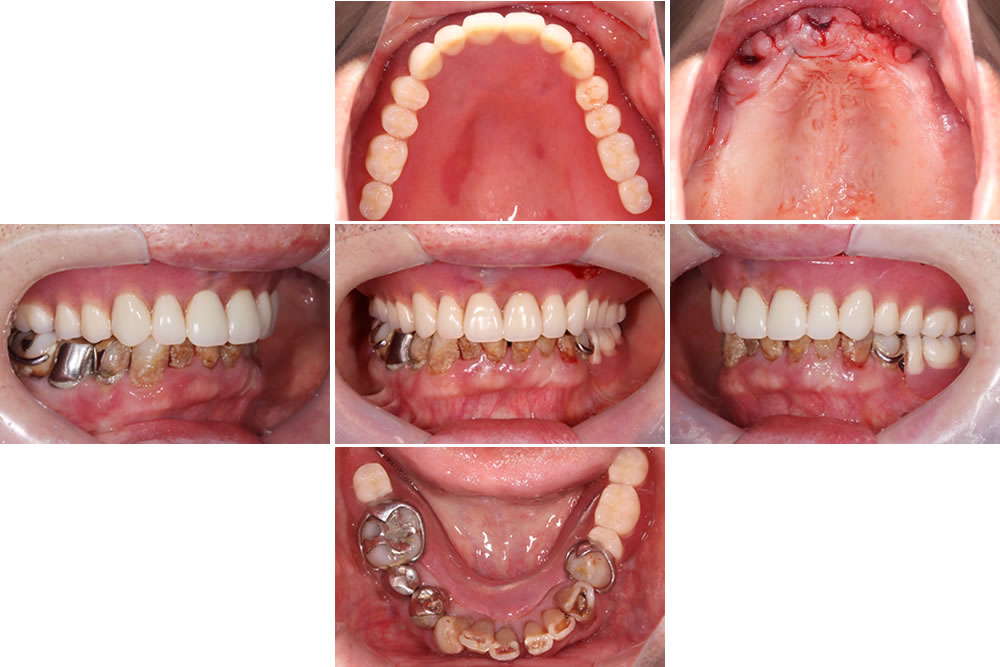

治療終了時の口腔内

下顎はインプラントおよびセラミックによる補綴治療を行い、上顎は保険適用の義歯を装着しています。

治療前後の比較

術前と比較して咬み合わせが安定しました。歯の傾斜も改善され、審美的にも患者さまにご満足いただけました。下顎は補綴前に必要部位の根管治療を行っています。X線写真上、下顎右4番の根尖病変は縮小傾向を示しています。